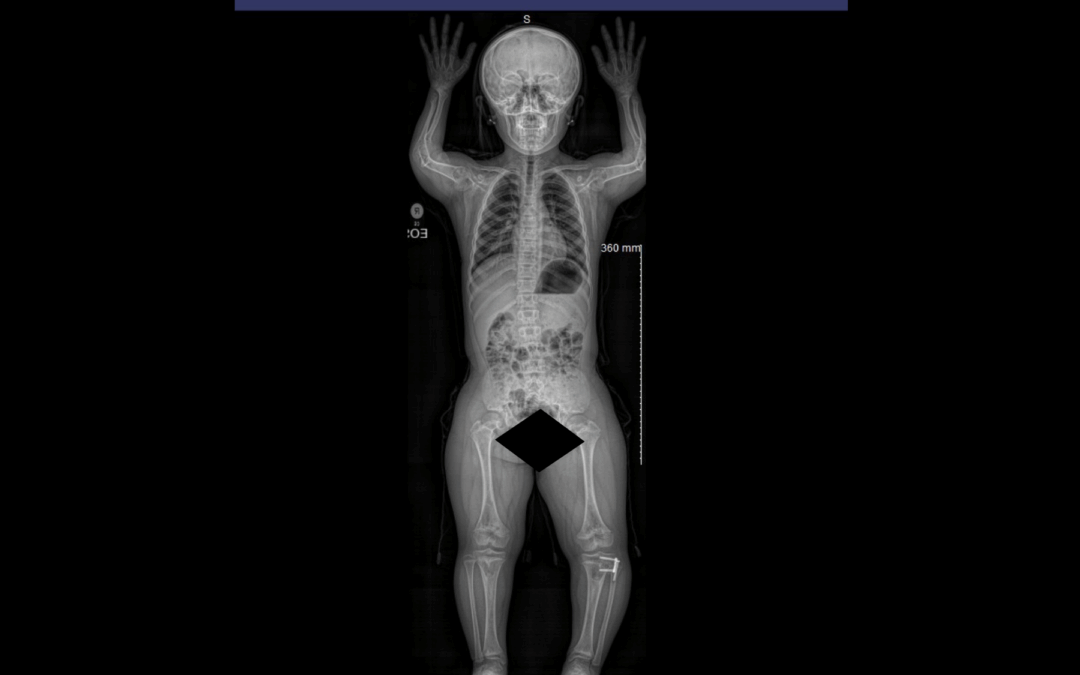

Understanding the Adult Achondroplasia Spine Adults with achondroplasia, the most common form of dwarfism, often experience progressive spine problems that impact mobility, comfort, and independence. The same skeletal characteristics that define the condition:...

Understanding the Achondroplasia Spine Achondroplasia is the most common form of skeletal dysplasia, caused by a genetic change in the FGFR3 gene that affects bone growth. While children with achondroplasia have average intelligence and life expectancy, their bone...